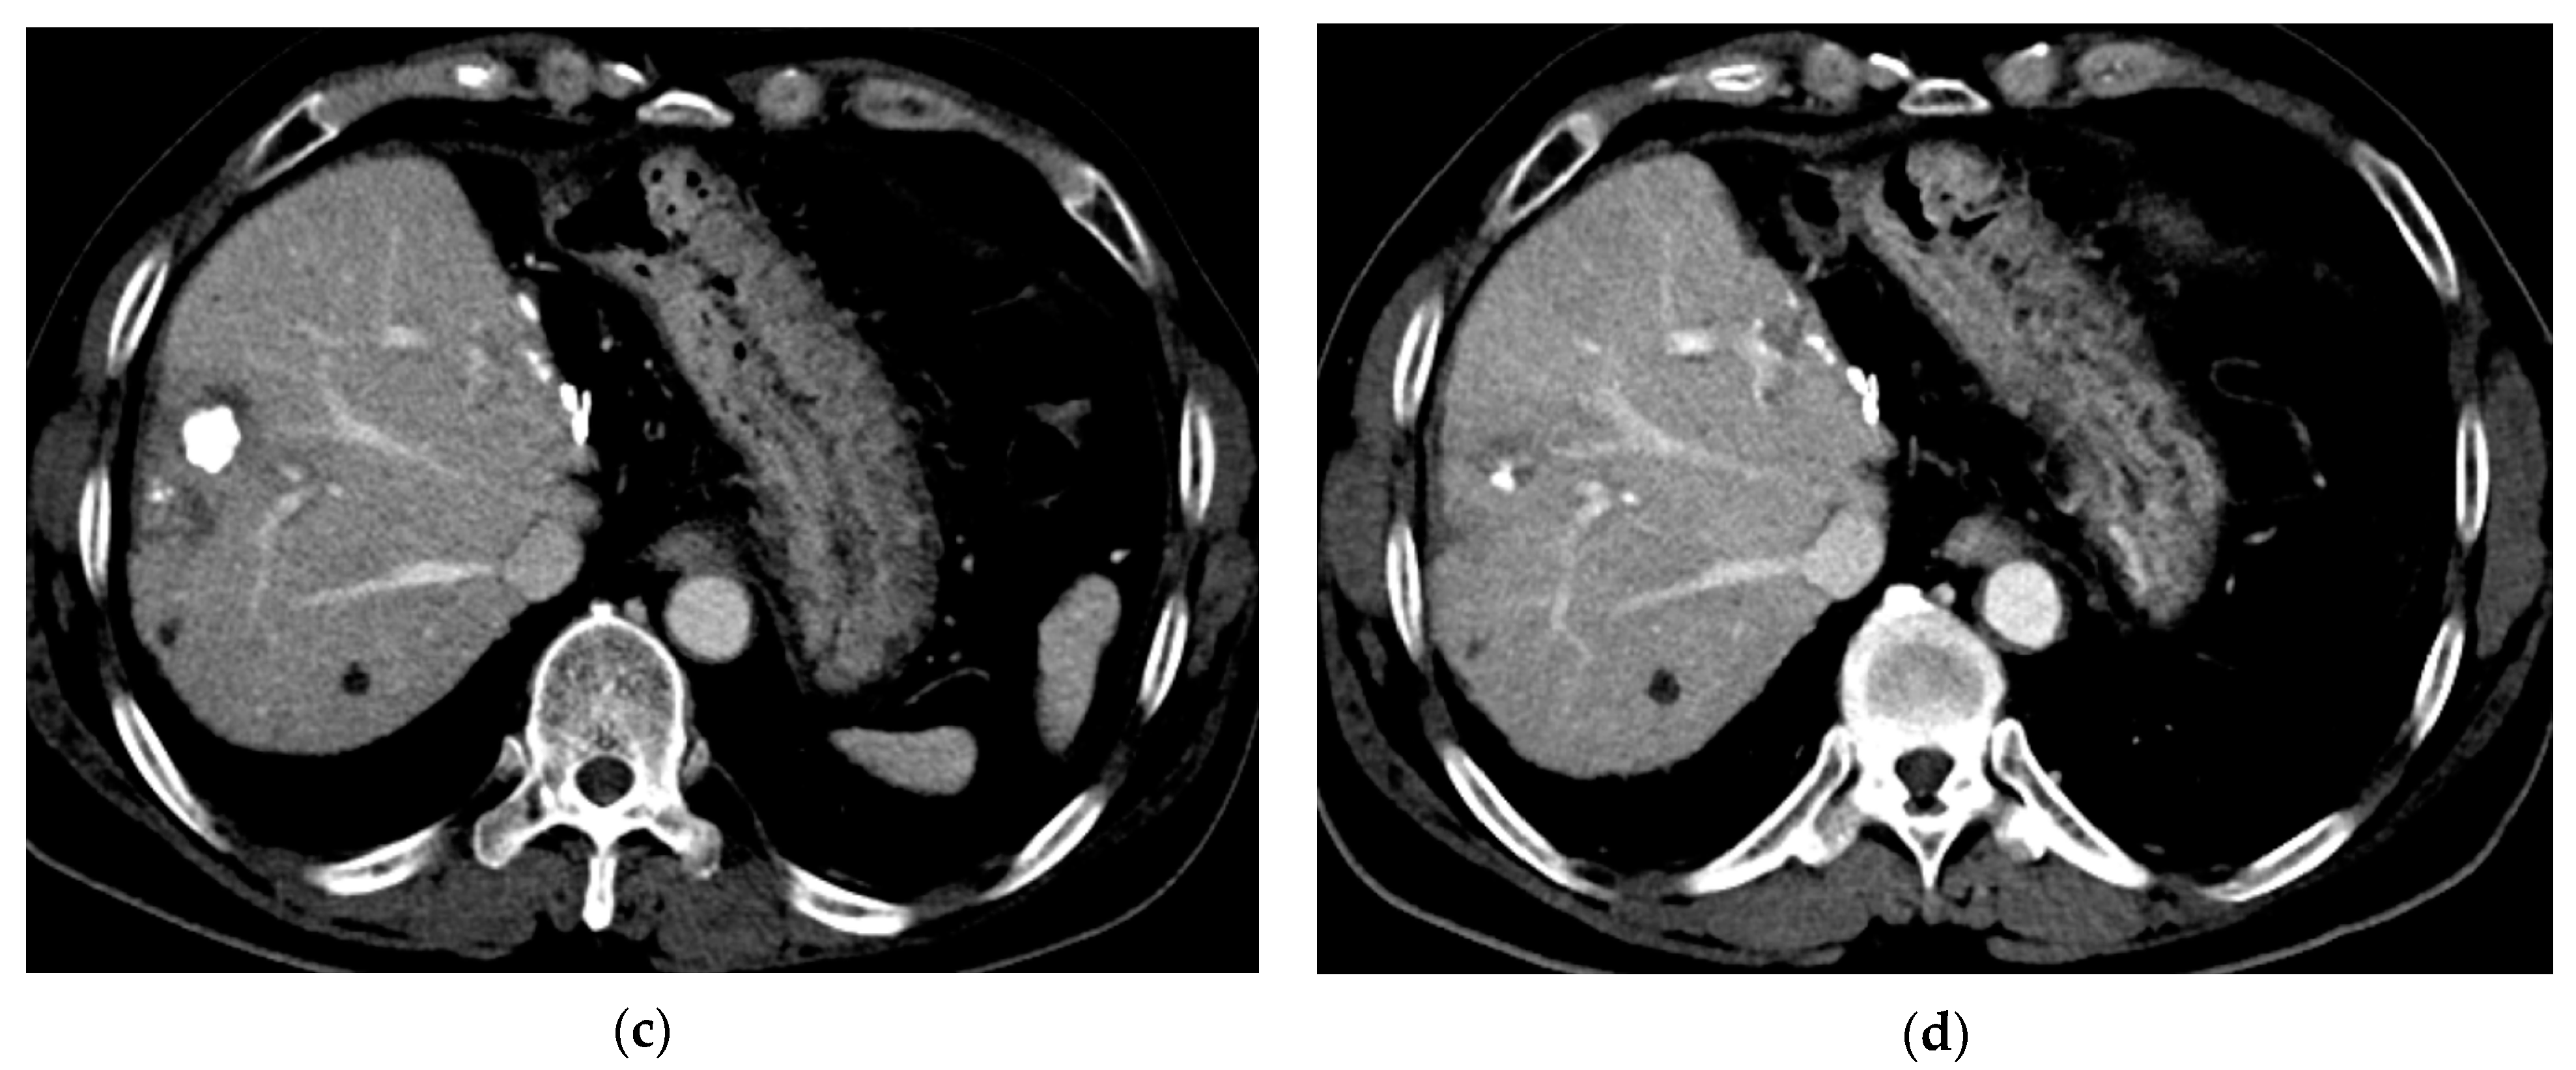

3.3. Local Recurrence